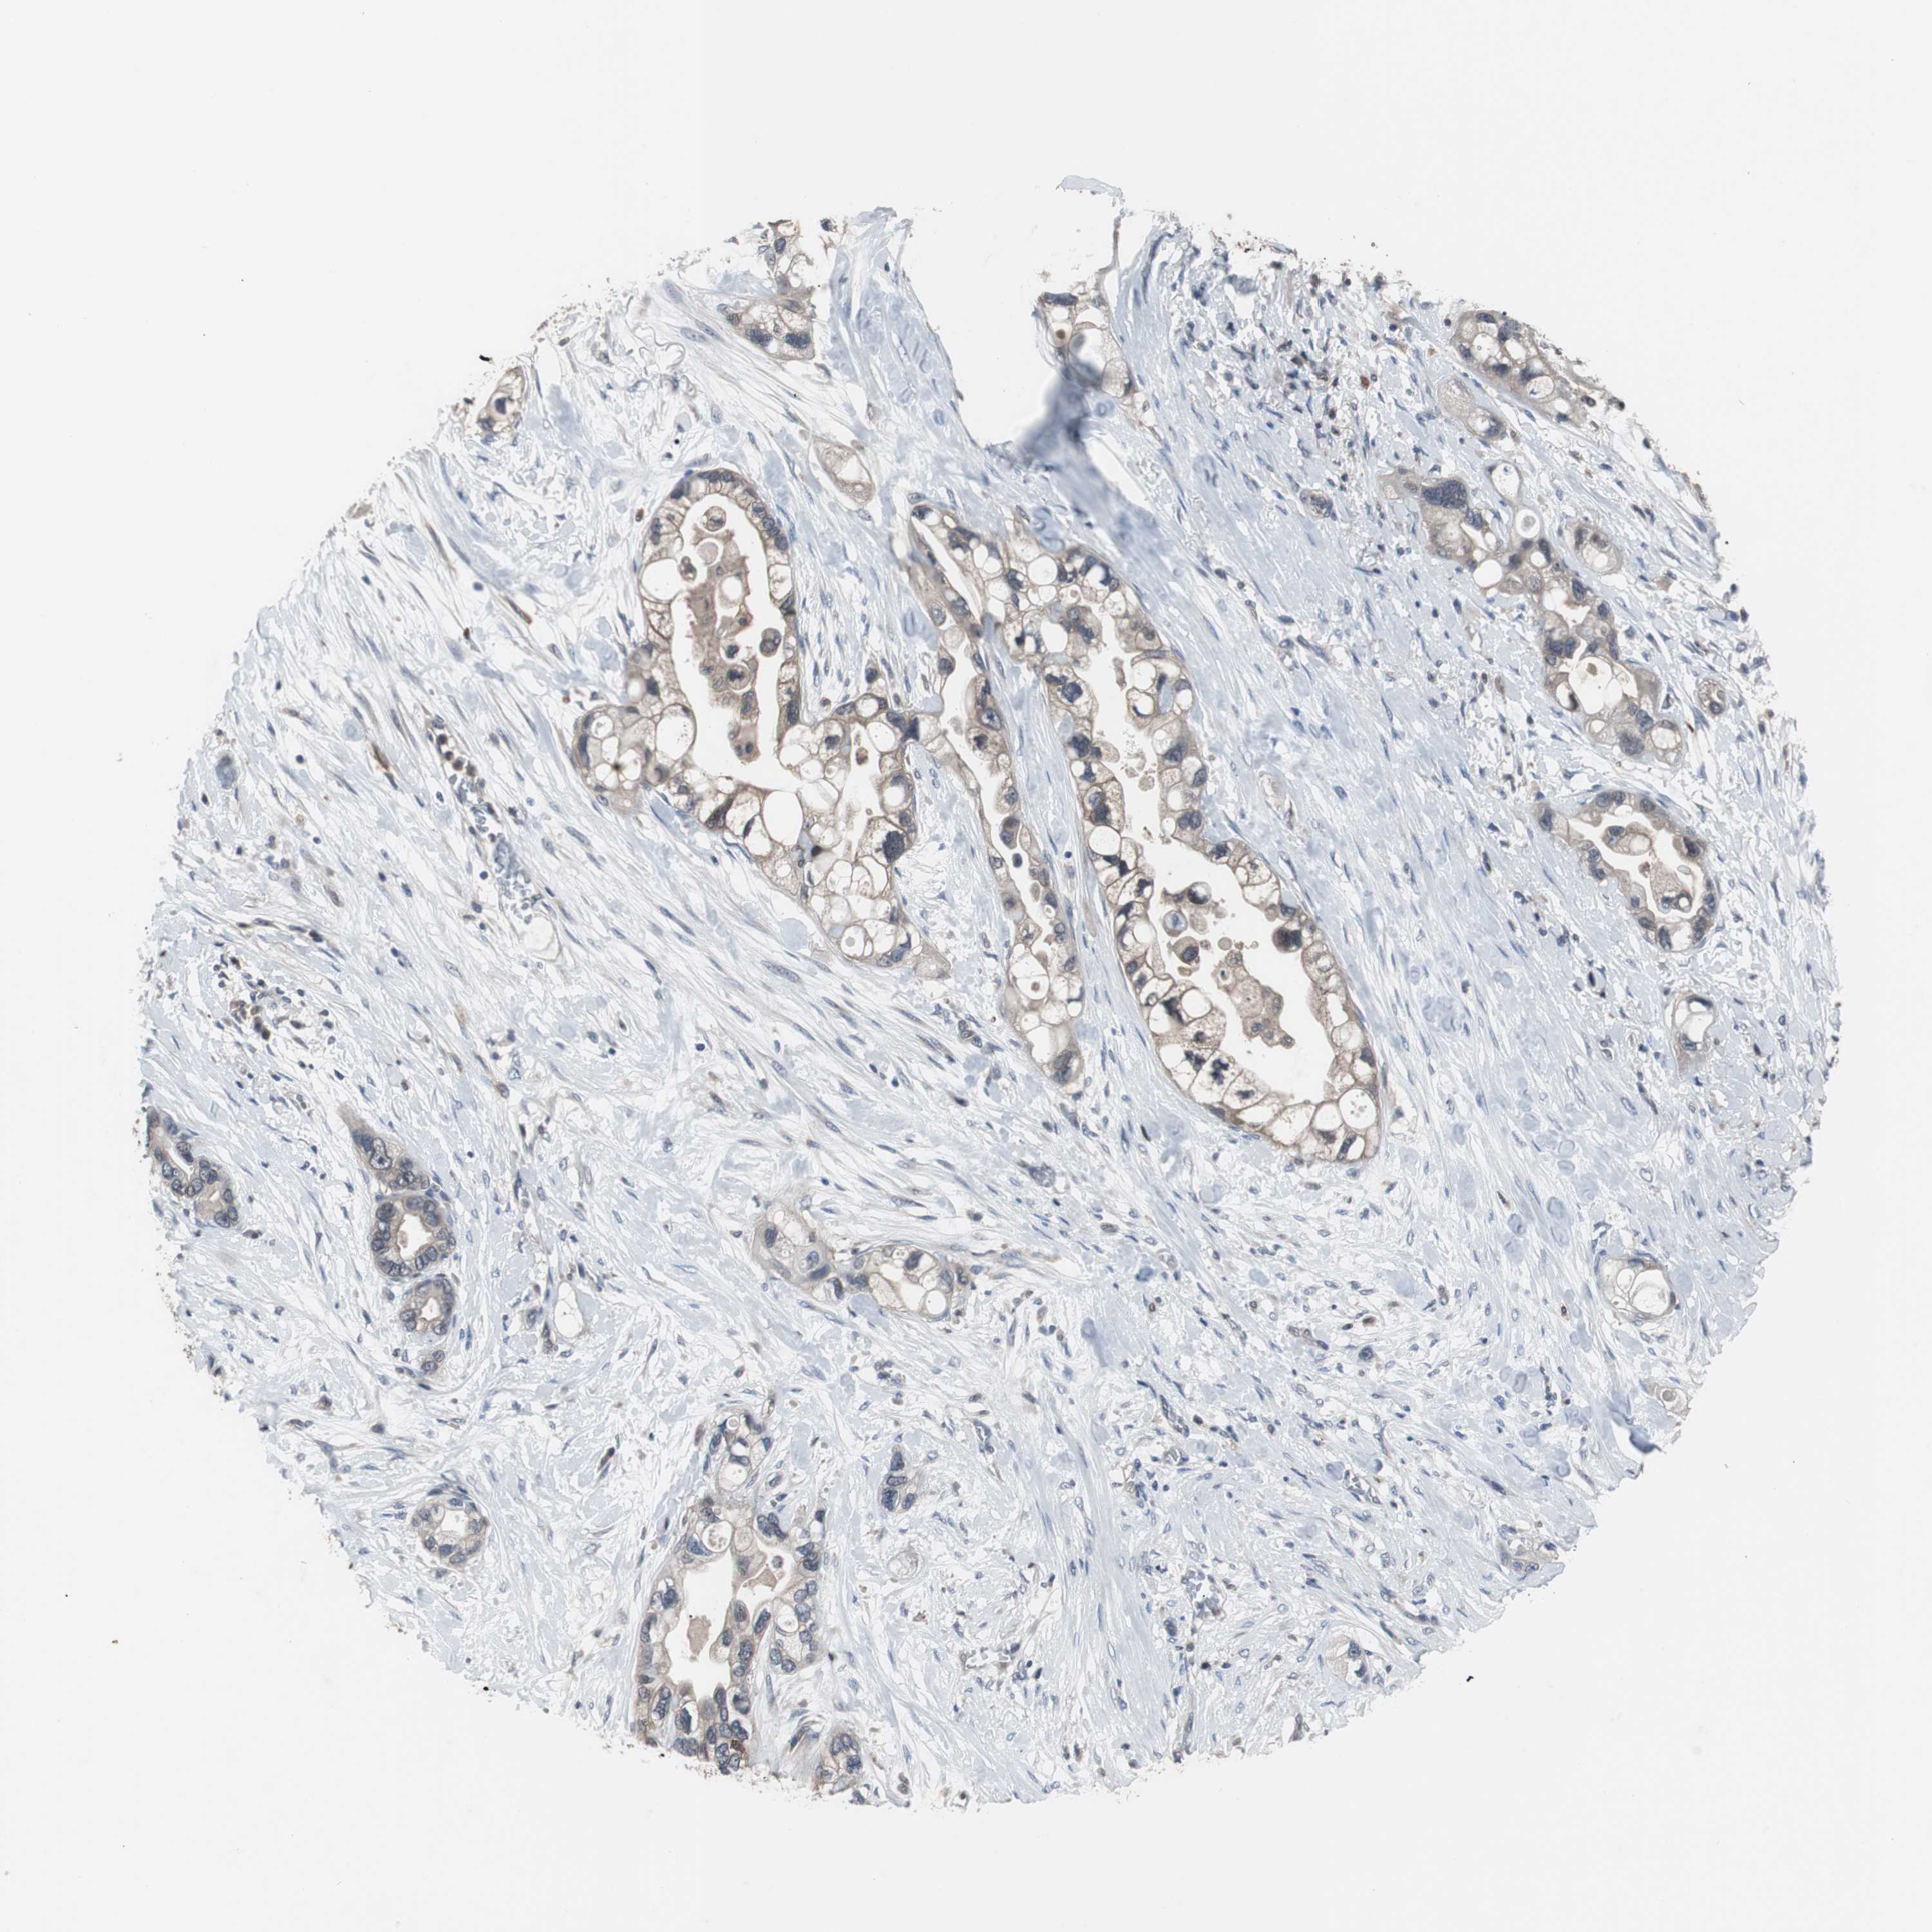

PANCREATIC CANCER - Protein expressioni

A mouse-over function shows sample information and annotation data. Click on an image to view it in a full screen mode. Samples can be filtered based on level of antibody staining by selecting one or several of the following categories: high, medium, low and not detected. The assay and annotation is described here.

Note that samples used for immunohistochemistry by the Human Protein Atlas do not correspond to samples in the TCGA dataset.

Antibody stainingi

Antibody staining in the annotated cell types in the current human tissue is reported as not detected, low, medium, or high, based on conventional immunohistochemistry profiling in selected tissues. This score is based on the combination of the staining intensity and fraction of stained cells.

Each image is clickable and will lead to virtual microscopy that enables deeper exploration of all samples and also displays staining intensity scores, fraction scores and subcellular localization as well as patient and tissue information for each sample.

Antibody HPA003565

Antibody CAB005312

Staining

High

Medium

Low

Not detected

Intensity

Strong

Moderate

Weak

Negative

Quantity

>75%

75%-25%

<25%

None

Location

Nuclear

Cytoplasmic/membranous

Cytoplasmic/membranous,nuclear

Adenocarcinoma, NOS

Adenocarcinoma, metastatic, NOS